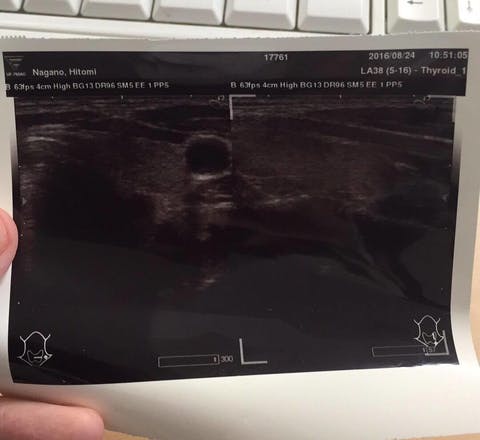

結果です。

「がん、ないよ」

甲状腺の左様、真ん中に確かにあった、がんは、すっかり消えてなくなっていました!!

「うそ~!!消えたってことですか?」

びっくりしました。こんなことって本当にあるんですね。

大きくなっていなきゃいいやって思っていましたが、まさか消えているなんて。